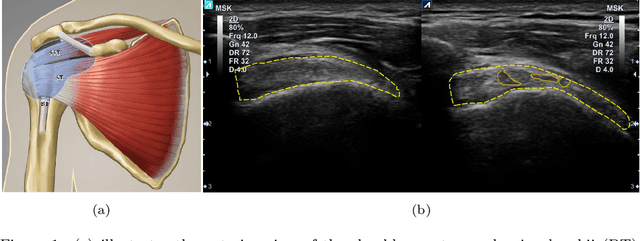

Abstract:Tendon injuries like tendinopathies, full and partial thickness tears are prevalent, and the supraspinatus tendon (SST) is the most vulnerable ones in the rotator cuff. Early diagnosis of SST tendinopathies is of high importance and hard to achieve using ultrasound imaging. In this paper, an automatic tendinopathy recognition framework based on convolutional neural networks has been proposed to assist the diagnosis. This framework has two essential parts of tendon segmentation and classification. Tendon segmentation is done through a novel network, NASUNet, which follows an encoder-decoder architecture paradigm and utilizes a multi-scale Enlarging cell. Moreover, a general classification pipeline has been proposed for tendinopathy recognition, which supports different base models as the feature extractor engine. Two feature maps comprising positional information of the tendon region have been introduced as the network input to make the classification network spatial-aware. To evaluate the tendinopathy recognition system, a data set consisting of 100 SST ultrasound images have been acquired, in which tendinopathy cases are double-verified by magnetic resonance imaging. In both segmentation and classification tasks, lack of training data has been compensated by incorporating knowledge transferring, transfer learning, and data augmentation techniques. In cross-validation experiments, the proposed tendinopathy recognition model achieves 91% accuracy, 86.67% sensitivity, and 92.86% specificity, showing state-of-the-art performance against other models.